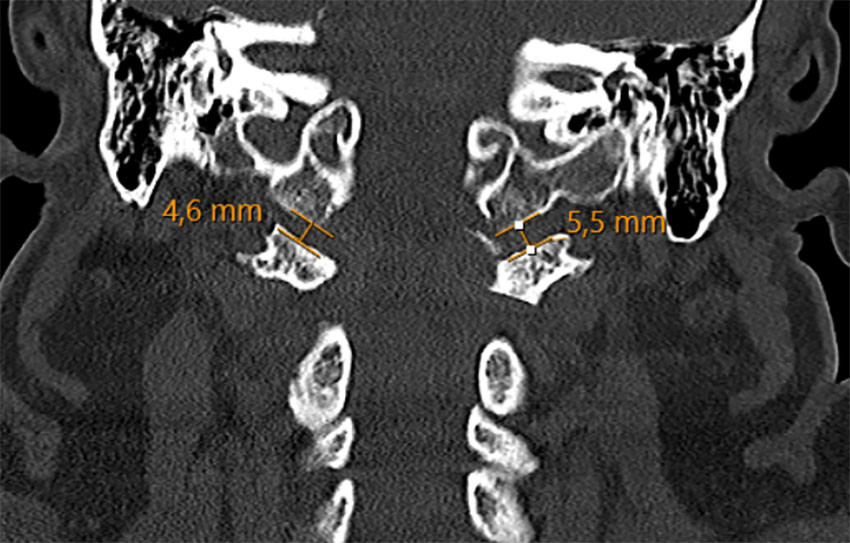

CT-undersøkelse av nakkesøylen viste en avulsjonsfraktur ved venstre oksipitalkondyl med translasjon og økt leddspalte i atlanto-oksipitalleddet – målt til 5,5 mm på venstre og 4,6 mm på høyre side (normalverdi < 1,5 mm (1)) (figur 1). Basion-dens-avstanden (BDI) ble målt til 20,2 mm (normalverdi < 8,5 mm (2)) (figur 2). Undersøkelse med magnetisk resonans (MR)-avbildning av nakkesøylen ble utført for nærmere vurdering av ligamentære strukturer, plassforhold for ryggmargen og for å kartlegge eventuelle tilleggsskader. Undersøkelsen viste uttalt prevertebral bløtvevshevelse og en ventral epidural væskeansamling uten tegn til kompresjon av ryggmargen. Det ble ikke påvist patologiske signalforandringer i ryggmargen. Alarligamentene lot seg ikke visualisere, noe som tydet på betydelig skade. På bakgrunn av bildefunnene stilte man diagnosen ustabil kraniocervikal dissosiasjon (craniocervical dissociation, CCD), klassifisert som type 2 i Traynelis-klassifikasjonen for atlanto-oksiptale dislokasjoner (3) – en separasjon mellom skallen og øvre del av nakkesøylen.